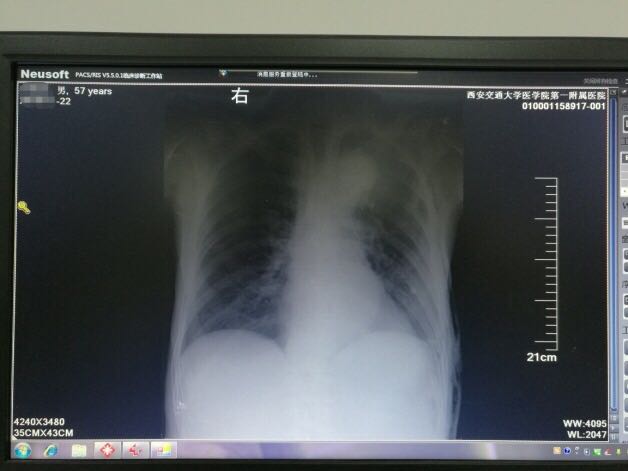

术后 1 周,复查胸片,左侧胸腔积液清除,患者症状消失,满意出院。